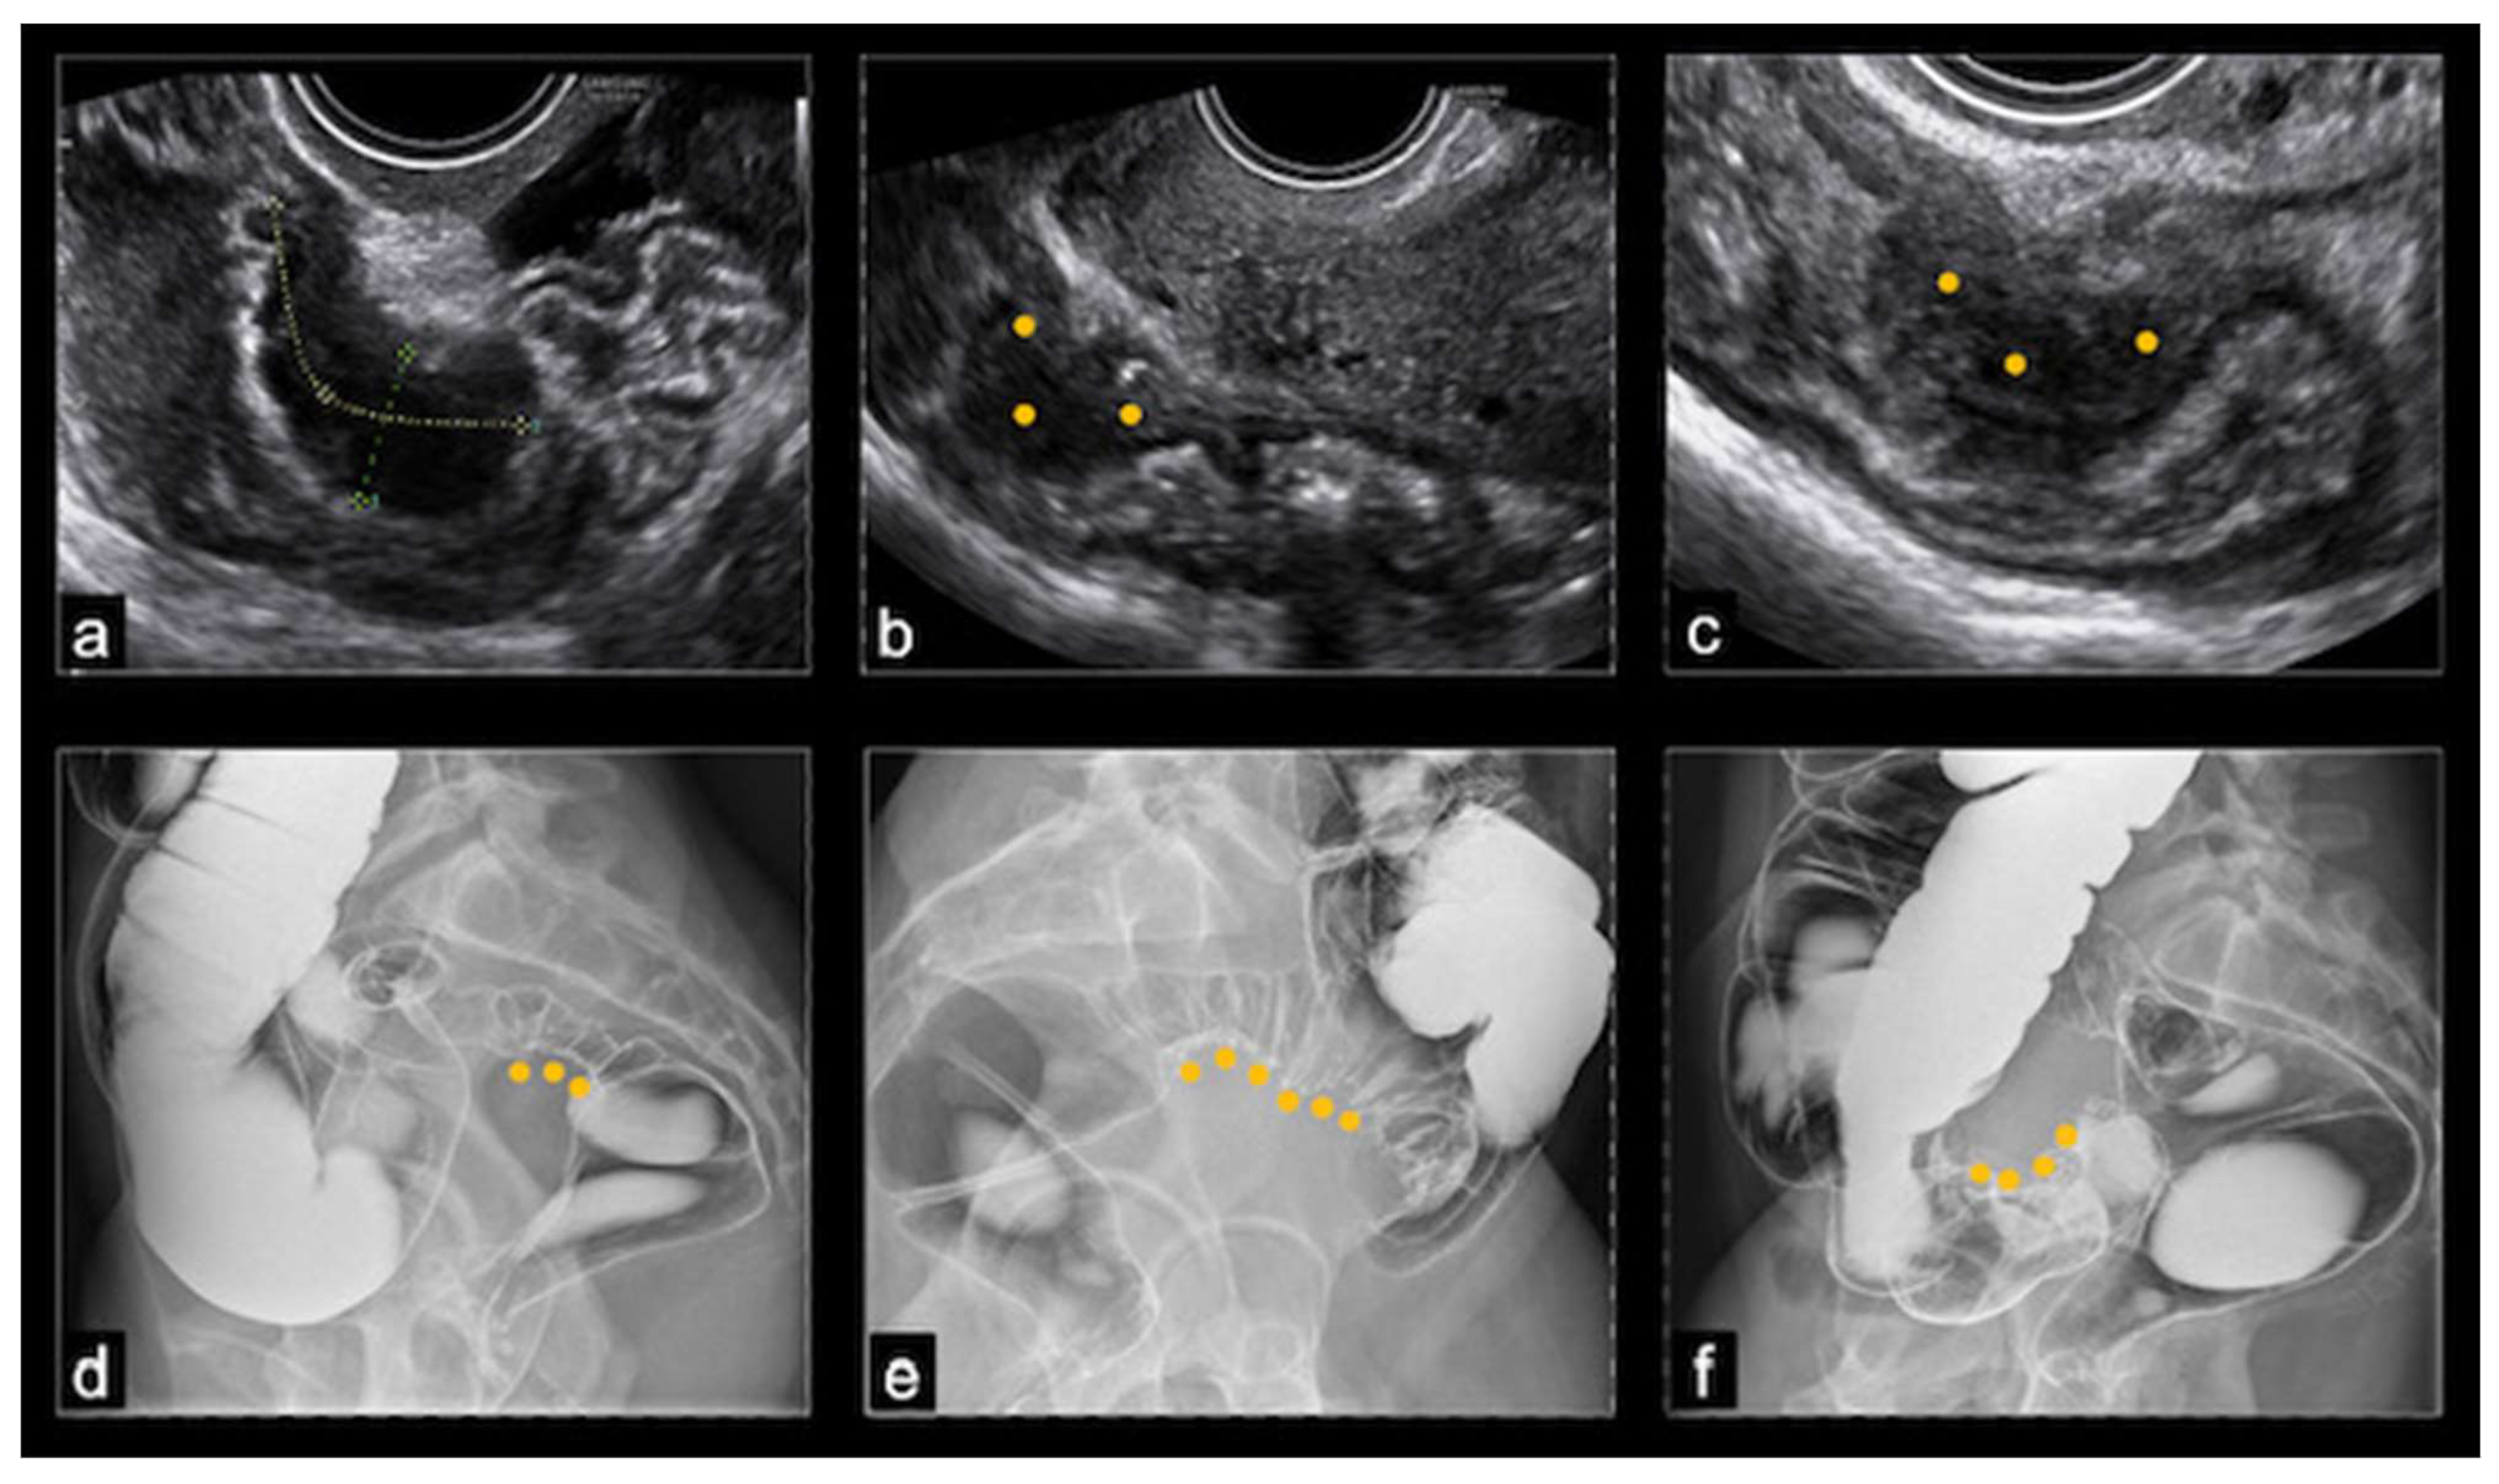

At ultrasound, BE usually appeared as a thickening of the hypoechoic muscularis propria or as hypoechoic nodules with irregular margins, without detectable blood flow at color Doppler. Nodules located above the level of the uterine fundus were considered sigmoid lesions, those located at the level of the uterine fundus were denoted as rectosigmoid junction lesions, and those below this level were considered rectal lesions. The dimensions of the nodules were recorded in three orthogonal planes, but in this study, only the largest measurement was considered. The rising of a nodule towards the lumen of the bowel indicated the possibility of (sub)stenosis. The final nodule dimension was a mean of the dimensions reported by TVS and DCBE, while the degree of stenosis was evaluated only by the DCBE (Figure 1).

Figure 1. (a-c) Ultrasonographic images of rectal nodules causing an estimated stenosis of 30-40%; (d) barium enema image of a recto-sigmoid junction nodule causing an estimated stenosis of 30-50%; (e) barium enema image of a sigmoid nodule causing an estimated stenosis of superior to 50%; (f) barium enema image showing a cecal nodule.